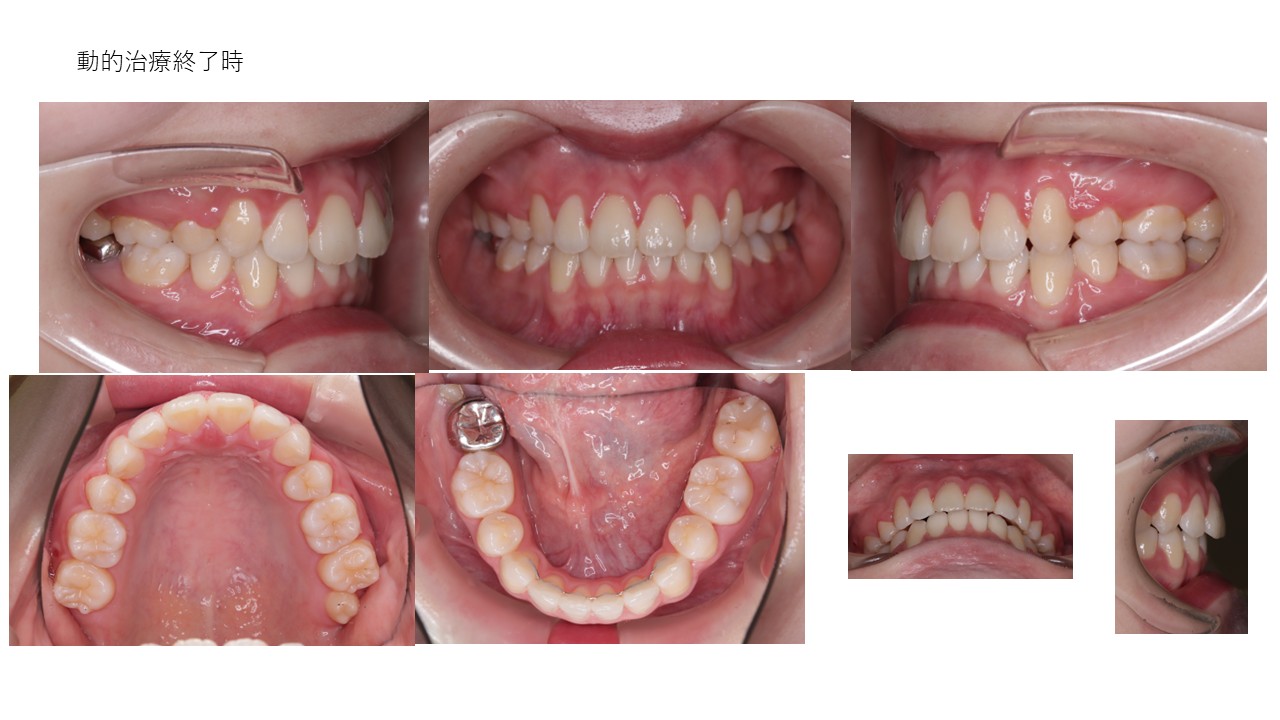

裏側ワイヤー矯正

| 主訴 | 叢生、前突 |

|---|---|

| 年齢 | 30代 |

| 治療期間 | 1年(継続中) |

| 治療回数 | 12回 |

| 治療に用いた主な装置 | カスタムメイド型リンガルブラケットデジタル矯正装置(WIN) |

| 治療費 | 1,300,000円(税別) |

| リスク・副作用 |

1. 矯正装置を装着すると、不快感や痛みが生じることがあります。通常、数日〜1週間ほどで痛みが消失し、慣れることが多いです。 2. 歯の動き方には個人差があり、予想された治療期間より長引く可能性があります。 |